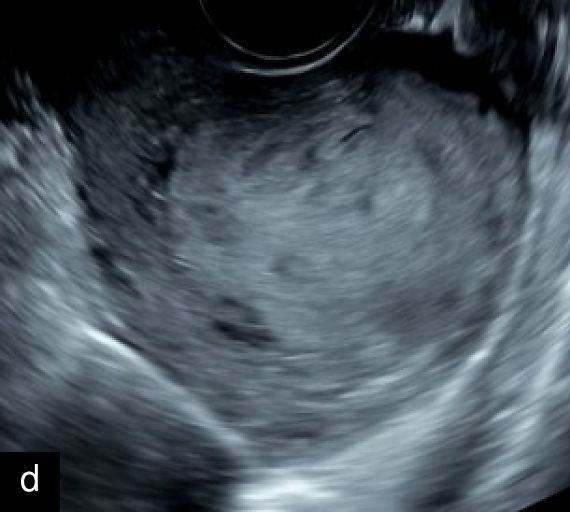

3

Transvaginal (a) and transabdominal (b) ultrasound images of uterine sarcoma. The lesion exhibits heterogeneous echotexture, irregular margins and peripheral vascularity on color Doppler. While uterine sarcomas are often highly vascularized, cases with lower vascularization can pose challenges in the differential diagnosis from benign myometrial lesions, such as atypical leiomyomas.